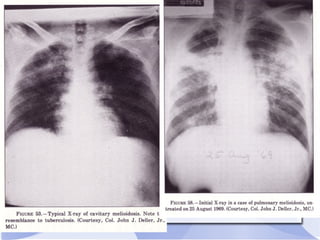

Imaging : CXR

● +46 % pneumonia

● +56% unilateral

pulmonary

shadowing

(predominant Rt

lung)

● +44% bilateral

lesions

● +14%cavitation-

● +Rt lobe and Lower

commonest

How to diagnose? Laboratory diagnosis 1. blood – culture 2. urine 3. pus 4. sputum Serological test 1. Agglutination test 2. Immunoflourescence Imaging : CXR Gold standard ● Isolation of B.pseudomallei from bodily fluids of patients

● +46 %pneumonia ● +56% unilateral pulmonary shadowing (predominant Rt lung) ● +44% bilateral lesions ● +14%cavitation- ● +Rt lobe and Lower commonest